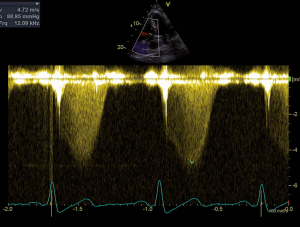

Abb. 2: CW-Doppler-Signal des Flusses durch die Trikuspidalklappe

Es zeigt sich ein schneller systolischer Regurgitationsjet. Der daraus errechnete systolische Druckgradient zwischen rechtem Ventrikel und rechtem Atrium liegt bei 89mmHg, was für eine schwere pulmonalarterielle Hypertonie spricht.